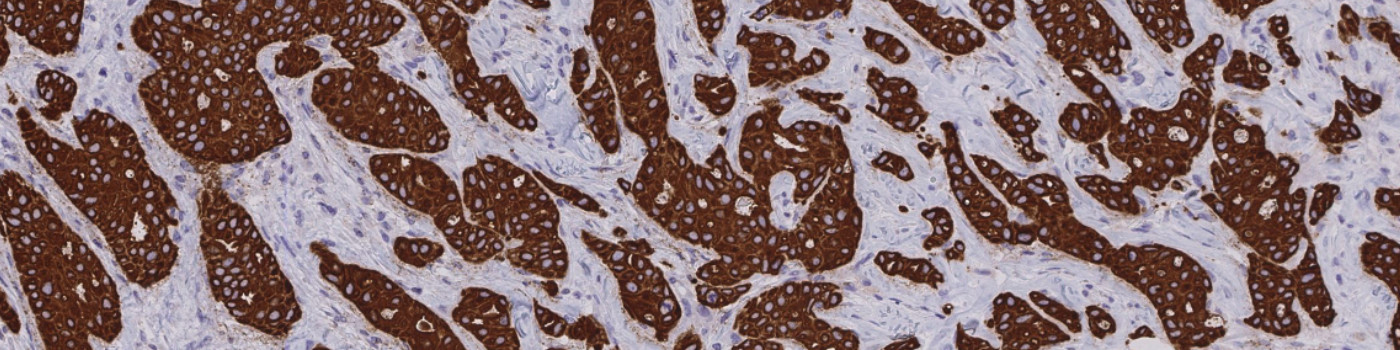

Two serial sections stained for ER/PR/Ki-67 and Pancytokeratin (PCK), respectively, must be used in this APP. Tumor regions are identified automatically on the PCK stained slides and the outlined tumor region are overlaid on the biomarker stained slide, thus automatically outlining the tumor regions in the other stain.

Second, the tumor areas are automatically detected from the PCK slide and outlined as regions of interest (ROIs) (see FIGURE 4 and 5). The ROIs are then superimposed on the aligned ER/PR/Ki-67 tissue slide to outline the tumor region for subsequent analysis limited to the inside of the tumor regions.